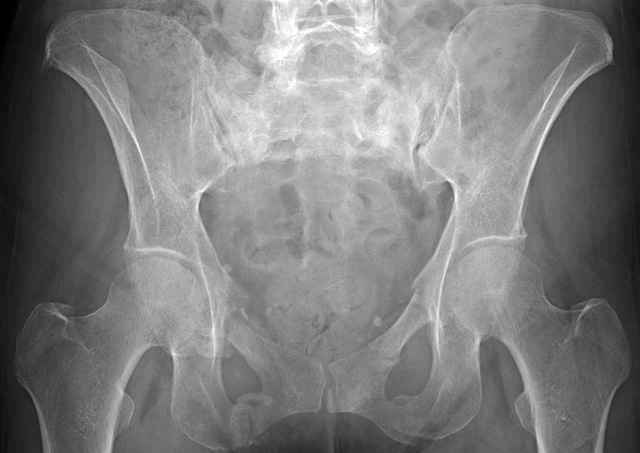

Percutaneous Fixation

(B) Ramus-Retrograde

2 TransIliac-TransSacral

Upper Segment